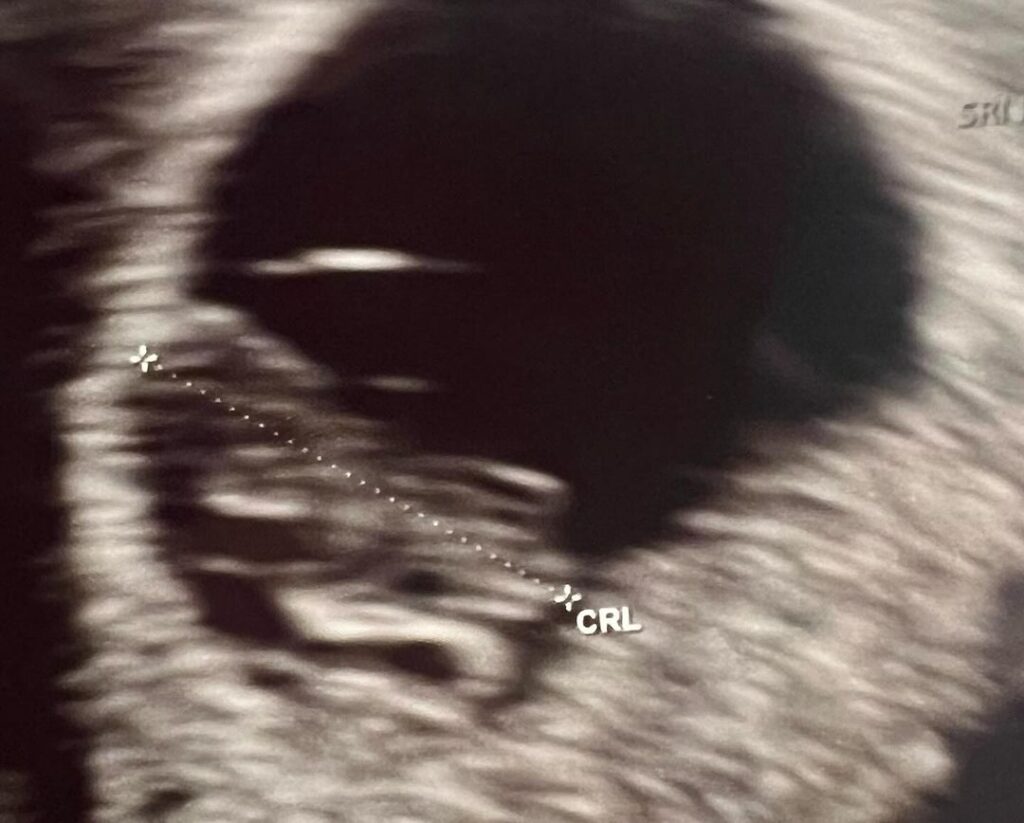

และล่าสุด พี่แจ็ค โพสต์ด้วยความอบอุ่นและความดีใจ ว่า วันนี้ได้ยินเสียงหัวใจเค้าครั้งแรก มันสะอื้นออกมาเอง มันอิ่มในใจ ใจมันฟูมาก ๆ คุณหมอบอก น้องโตเร็วมาก โตไวกว่าที่คุณหมอตั้งเกณฑ์ไว้ ลูกพ่ออออ ❤️❤️❤️❤️❤️❤️